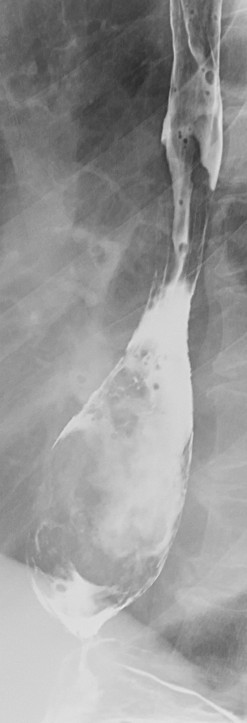

主诉:胸骨后隐痛40天,伴嗳气10天。 现病史:患者40天前无明显诱因出现胸骨后隐痛,呈间断性,无明显加重缓解因素,无放射痛。无进食哽噎感,无吞咽困难,无发热咳嗽,无胸闷心悸,无腹痛腹胀,无头晕头痛。10天前开始,患者出现嗳气不适,胸骨后疼痛无明显加重。于奈曼旗人民医院就诊,查纤维胃镜示“食管占位”。今为求进一步治疗,来我院就诊,门诊以“食管占位”为诊断收入院。患者病来一般状态好,小便正常,大便次数少,腹泻、便秘交替,饮食睡眠好,近期体重减轻约8KG。 。 既往史:否认高血压、冠心病、糖尿病等疾病史;否认肝炎结核等传染病病史;4年前颌面部外伤,否认手术史,否认输血史。否认食物及药物过敏史。预防接种史不详。

查体:T:36.4℃,P:78次/分,Bp:131/77mmHg,R:16次/分。神清语明,步入病房,查体合作,营养状态略差,皮肤粘膜无黄染,结膜无苍白,浅表淋巴结未触及肿大,气管居中,胸廓对称无畸形,呼吸运动正常,双肺叩诊清音,未及明显罗音。心音钝,律齐。腹平软,无压痛及反跳痛,肝脾肋下未触及。肝区叩痛(-),双下肢无水肿,脊柱四肢活动无异常。 辅查:胃镜(奈曼旗人民医院,2015-10-28):食管占位。

诊断 : 食管占位 治疗:入院后完善相关检查,胃镜病理未能予以确定诊断为恶性肿瘤。患者家属拒绝再次胃镜病理检查,要求行手术治疗。 后为解除梗阻症状,提升患者生活质量,按食管恶性肿瘤准备行手术治疗,术中切除肿物并剖开,内部质韧,肿物表面局部溃疡性改变,冰冻回报:平滑肌瘤伴鳞状细胞癌,患者现术后康复中,病理尚未回报。

患者为食管间叶来源肿物恶性,还是食管平滑肌瘤伴发食管癌,希望术后病理能给予进一步解答。